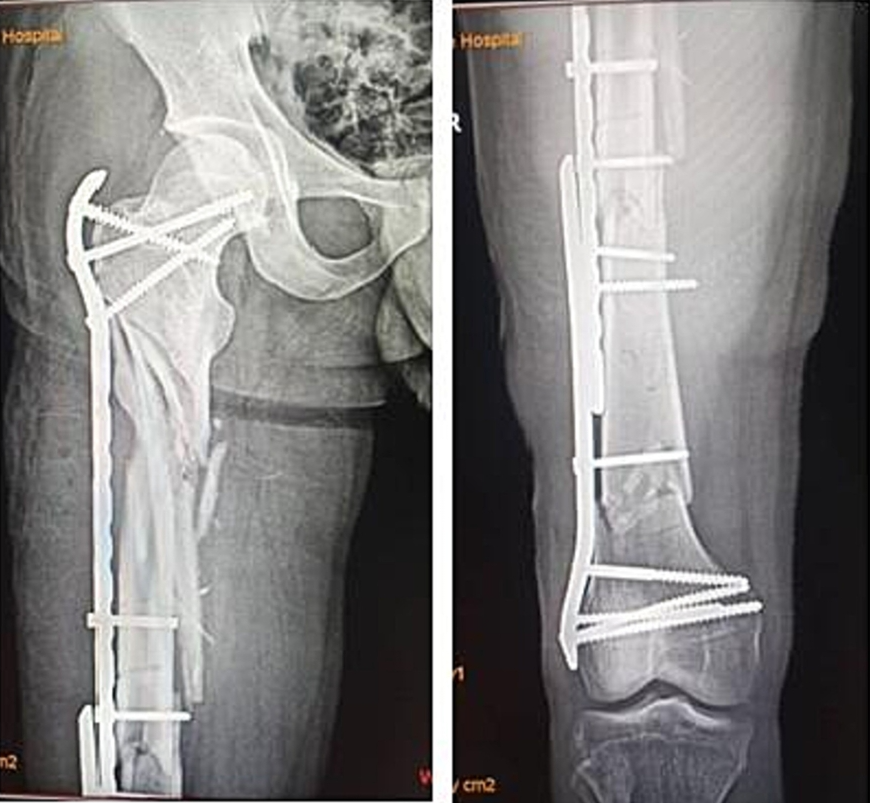

一,背景:复杂股骨骨折是指股骨干合并近端或远端骨折的复合型损伤,仅占所有股骨骨折的5%,治疗极具挑战性。单一内固定方案常难以实现有效固定,现有文献报道了多种治疗方式但疗效参差不齐。本病例报告展示了一例股骨近端严重粉碎性骨折合并远端节段性骨折的患者,其骨折极不稳定需手术治疗。据我们所知,此类复杂骨折类型在文献中极为罕见,关于其固定方式的报道几乎空白。本例采用微创双钢板重叠固定技术,分别于骨折区域上下方应用桥接型股骨近端锁定钢板与刚性股骨远端锁定钢板。二,案例:一名38岁男性患者因交通事故致右大腿闭合性损伤,表现为疼痛、畸形、肿胀及无法负重,至我院急诊就诊。患者为轿车后排乘客,车辆高速行驶时右侧遭受正面碰撞。查体见右大腿明显肿胀伴压痛。右大腿平片显示:右股骨近端节段性粉碎骨折合并远端两处横行骨折(图1)。采用微创钢板接骨术。经三个外侧切口显露股骨(图2)。采用间接复位技术,实现近端骨块的相对对位,并在透视引导下置入两块锁定钢板:股骨近端锁定钢板(PFLP)采用顺行置入,股骨远端锁定钢板(DFLP)采用逆行置入。两钢板重叠区域通过两枚皮质骨螺钉经对应孔道实现骨固定(图3)。术后给予镇痛药物、深静脉血栓预防及抗生素预防治疗,患者恢复顺利。引流管于术后第2天拔除,指导患者使用腋拐行走,右下肢禁止负重。术后第5天出院,嘱2周后返院拆线。在物理治疗师指导下,分别于术后6周及12周开始部分负重及完全负重行走。术后即刻X线片显示内固定位置良好(图4)。桥接钢板固定的近端区域可见四皮质骨痂形成,术后6个月(图5)及9个月(图6)X线片。远端节段性骨折线呈渐进性消失,术后9个月X线片显示骨折线完全消失(图6)。三,总结:此类复杂性股骨骨折属于罕见的高能量创伤。本文报道了采用微创双钢板接骨术成功治疗复杂股骨骨折的案例,结果显示骨折及时愈合且临床疗效良好。文献来源:Kabiru Salisu, Ifeanyi Kene Aghadi,Minimally invasive dual plating of a complex femoral fracture; a case report,Trauma Case Reports,Volume 43,2023,100768,ISSN 2352-6440, https://doi.org/10.1016/j.tcr.2023.100768.